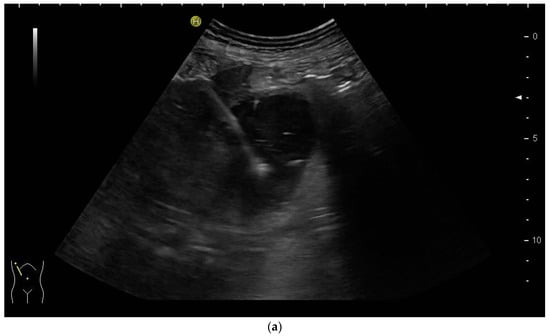

Most authors recommend a transhepatic approach in order to prevent biliary leakage to the abdominal cavity during drainage or after removal of drainage [43,55,56,76,77] (Figure 9).

Figure 9.

(a) Transhepatic puncture of an inflamed gall bladder in the in-plane technique. The Chiba needle is depicted well; (b) A few days later, laparoscopic cholecystectomy was performed. The drainage ran through Segment V of the liver. It was removed without provoking biliary leakage from the liver parenchyma.

The consideration is that a perforation in the hepatic surface of the gallbladder will be covered by the liver tissue after the removal of the drain. However, retrospective analyses comparing the transhepatic route with the transperitoneal (i.e., nontranshepatic) access (Figure 10) report no differences in the complication rates [58,78,79].

Figure 10.

PGBD without passing the liver and using the trocar technique: straightened drainage passes right below the lower liver margin into the gallbladder.

Again, the “in plane” approach is recommended to depict the needle in real time and continuously on its way. This is mandatory because iatrogenic perforation of the posterior gallbladder wall must be avoided. Both the drainage techniques, Seldinger (Figure 11a–c) and trocar (direct puncture, cf. Figure 10), may be used, depending on the physician’s preferences [43,58].